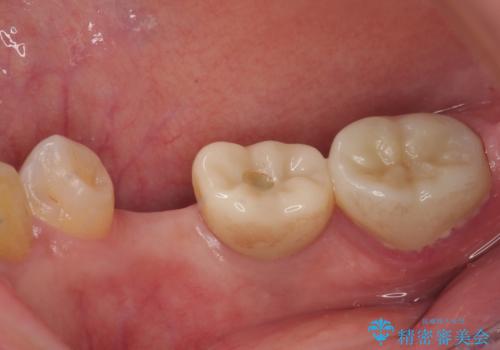

割れてしまった奥歯 インプラント治療

- 近医にて抜歯が必要と診断されたとのことで来院された患者様です。

術前の診査では、歯が破折している可能性が高いものの、確実に抜歯が必要と診断ができない状態でした。

状況次第では抜歯が必要となり、その際にはインプラント治療を行うことを了承いただいた上で、破折していない場合には根管治療を行うこととしました。

土台の材料を外して顕微鏡下で確認したところ、歯根にまで及ぶ破折が認められたため、インプラント治療を行うこととしました。

インプラント治療をきっかけに、銀歯を全てセラミックに替えていきました。